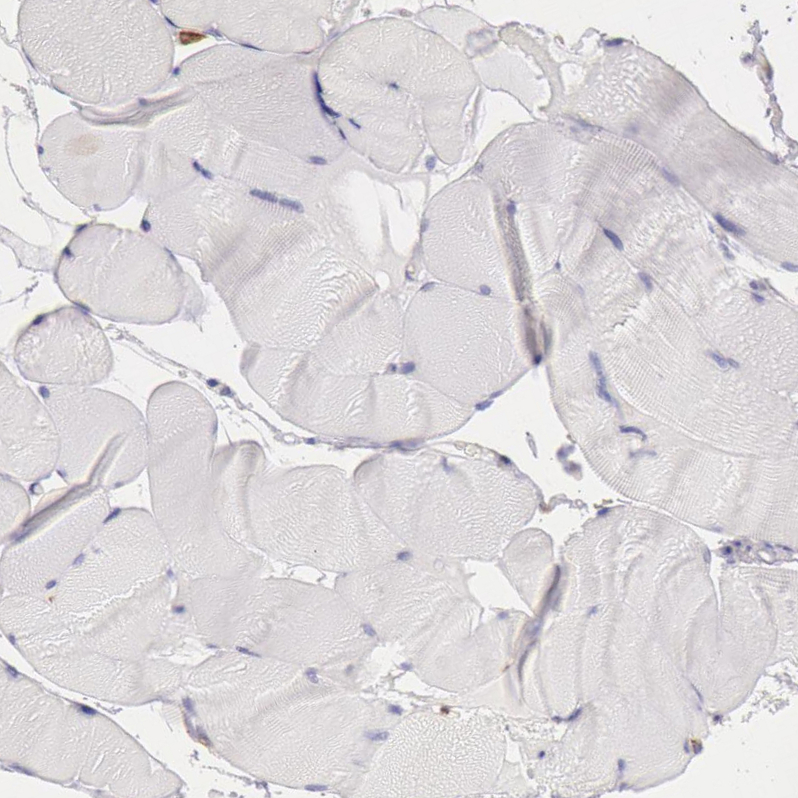

Immunohistochemical staining of human duodenum shows strong cytoplasmic positivity in lymphoid cells.